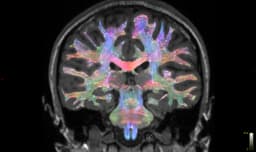

FDA Lumipulse pTau217 exploding (90% acc/AUC0.93 virtual PET MCI/early AD, 20yr pre-symp); Spear/Roche; WashU pTau217 clock; VeraBIND tau seeding 94/96%; ApoE ϵ4 99.6%; IFN-γ inflammation high AD/MCI APOEε4 tie; UEA gut-brain blood metabolites 79% MCI AI; Miller School AD/PD Copenhagen: APOE4 toxic, African ancestry haplotype cuts 75% AD risk in E4 homozygotes, ABCA7 ceramides; Lund ProtAIDe-Dx AI 81-95%; HABS-HD tau early memory areas Black/Hispanic sans amyloid disparities; DAC Global South equity; retinal OCT/OCTA AD vs VD; low-field MRI global access; speech/language AI dx; OSU real-time chem AD damage; ARIC/Galway VitD>30ng/mL midlife tau drop 16yrs; Sen. Klobuchar AADAPT Act virtual PCP training; Broadlawns IA mobile clinic FDA blood tests/nav; Tau Global Conf May14-15; CA SB950; Alz Assoc screening; non-memory signs risky/social/vision/personality changes; tau-sleep cycle.